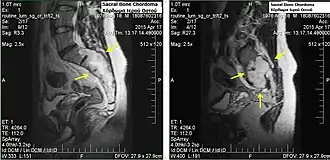

.jpg)